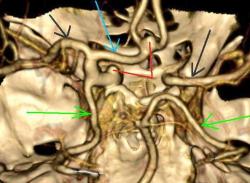

Женщина, 52 года. Жалобы на птоз слева. Направлена на КТ для исключения аневризмы сифона внутренней сонной артерии (ВСА). Травмы не было.

На КТ правая сонная артерия немного тоньше обычного, сифон продолжается в среднюю мозговую артерию. Правая задняя мозговая артерия отходит от основной артерии.

Левая общая сонная артерия гипертрофирована, на шейном уровне с патологической извитостью. Сифон также шире, чем справа. Задняя мозговая артерия отходит от супраклиноидного отдела ВСА - задняя трифуркация. Левая передняя мозговая артерия делится на две правую и левую передние мозговые артерии (задняя трифуркация), в развилке небольшая аневризма на широком основании. Вторая такая же аневризма на уровне отхождения глазной артерии.

Аневризмы - красные стрелки, Средние мозговые артерии - черные, Задние - зеленые, передняя мозговая - голубая стрелка.